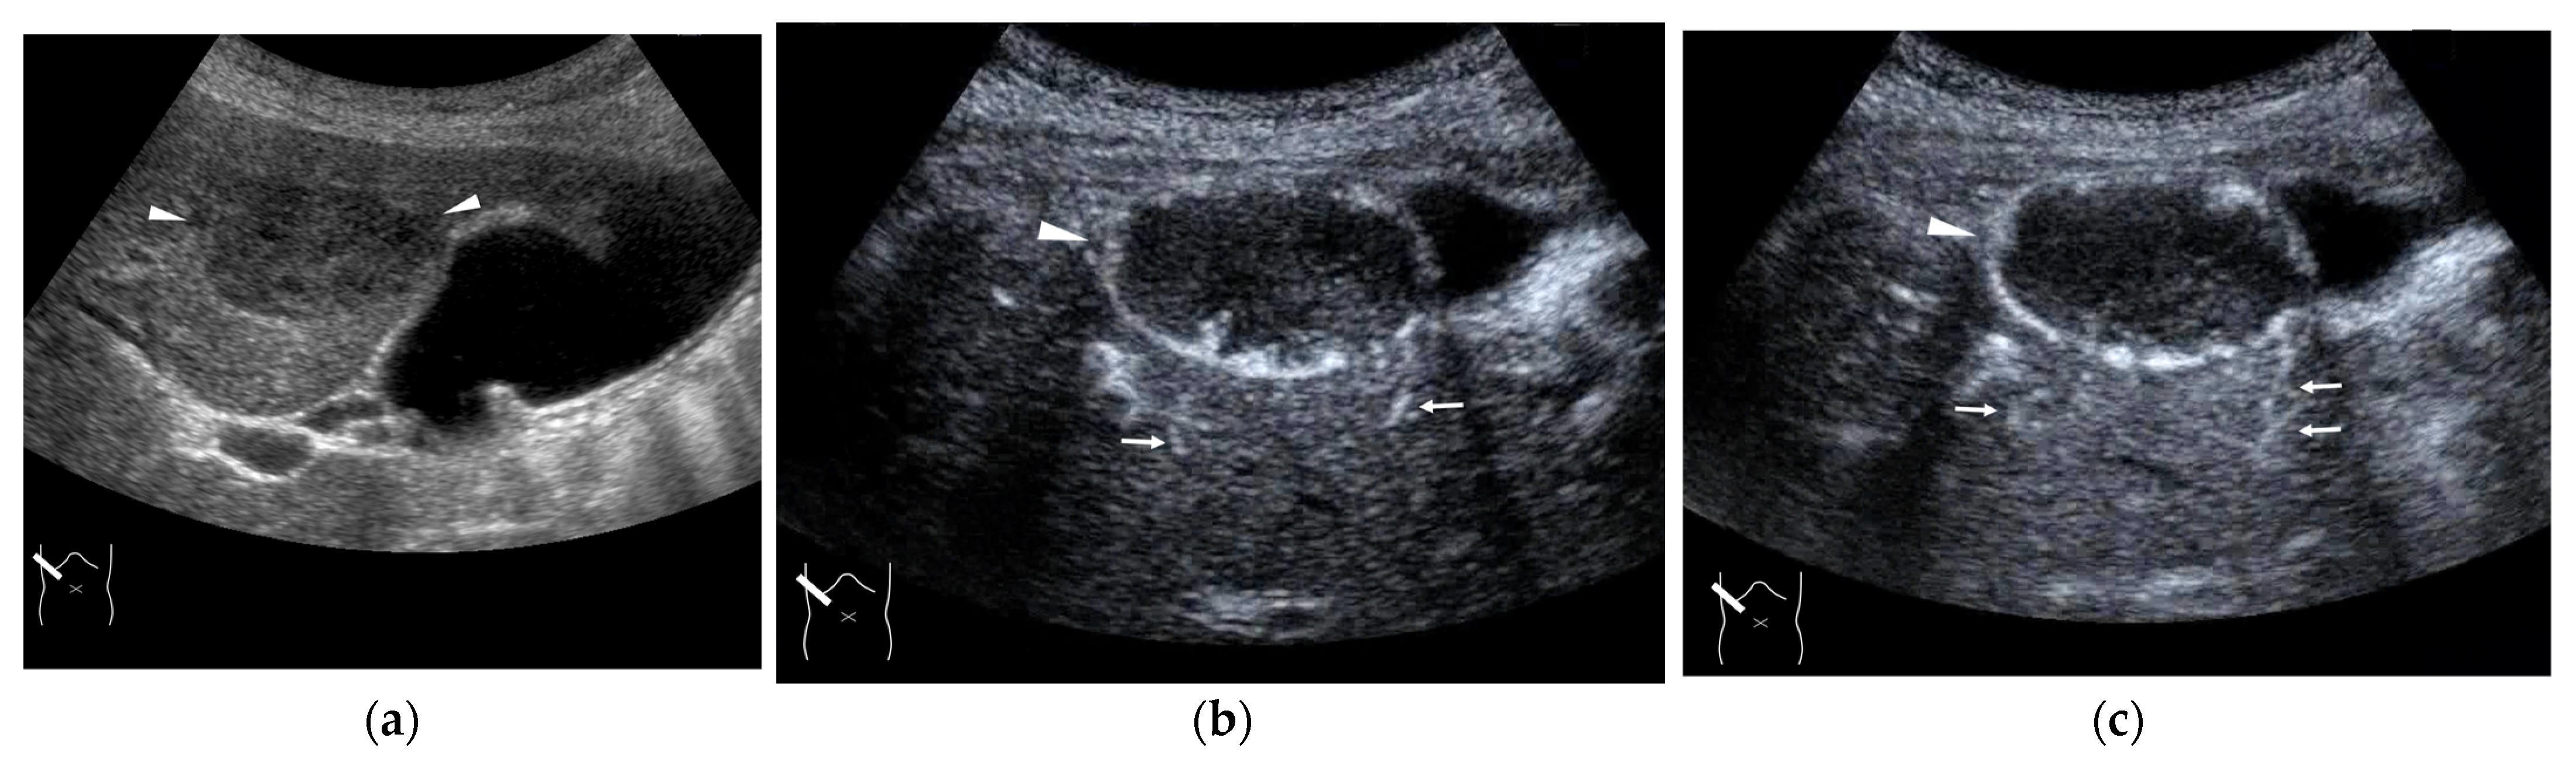

4.3. Budd–Chiari Syndrome

In a small number of cases, the cause of intrahepatic V-V shunts is congenital; they are seen mainly in a small number of HHT diseases. However, most of the V-V shunt cases are almost always acquired due to some form of HV occlusion, which can be clinically divided into two main types: HV thrombus and compression of a mass lesion (Figure 12) [52,53]. The V-V shunt is formed when an accidental stenosis or obstruction occurs at any point between the intrahepatic HV and inferior vena cava. On the other hand, in patients with a hepatic mass lesion, HVs are easily compressed by the mass because they have a thinner wall than other hepatic vessels (arteries and portal veins) and are easily affected by external pressure [54]. Simply speaking, V-V shunts occur when the responsible mass lesion, whether benign or malignant, exerts a large external compression force. Compared with the other intrahepatic shunts, V-V shunts have no important clinical implications. Thus, in the clinical setting, the precise diagnosis of V-V shunts serves to exclude the possibility of other shunts. The role of CEUS is to confirm the stenosis or complete occlusion of HVs and IVC; the result affects subsequent treatment strategies (Figure 13).

Figure 13.

Representative case of Budd–Chiari syndrome (type 1): (a) B-mode US shows many venous collaterals (arrow heads) in the left lobe. (b,c) Color Doppler US shows slow flows in these collaterals (yellow arrow heads). (d) CEUS confirms communication between these collaterals and intracapsular collaterals (arrows). (e) It confirms no blood flow in obstructed IVC (yellow arrow).